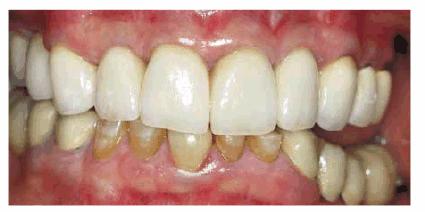

Figures 29-12A to C show a 75-year-old woman who presented

with severe root caries and moderate periodontal disease. Her daughter, who

disclosed that her mother was difficult to please, referred her. The daughter

was very supportive of her mother receiving dental treatment; however, her

mother was initially not interested. The mother did not think that the esthetic

aspect of dentistry was important. During consultation with the dentist, the

mother was informed of the infection in her mouth and the potential effect that

this could have on her future health and functionality. The patient consented

to have the maxillary arch restored with fixed prosthodontics. She refused to

accept treatment for her mandibular teeth, preferring to use her existing

partial denture. Figures 29-12D, and 29-12E show the final result after periodontal and

prosthodontic treatment. Although the patient was not particularly grateful to

have the dental treatment, her family was thrilled to have the caries infection

removed and the esthetic appearance improved. The patient lived with her

esthetically improved appearance for an additional 13 years.

Figure 29-12A to C: This 75-year-old woman had severe root caries and moderate periodontal disease.

Figure 29-12D: Although this woman stated that she would "just as soon have her teeth extracted," she was motivated to have both periodontal and prosthodontic treatment.

Figure 29-12E: The patient's smile after esthetic dental treatment shows just how much she appreciated her dental treatment.